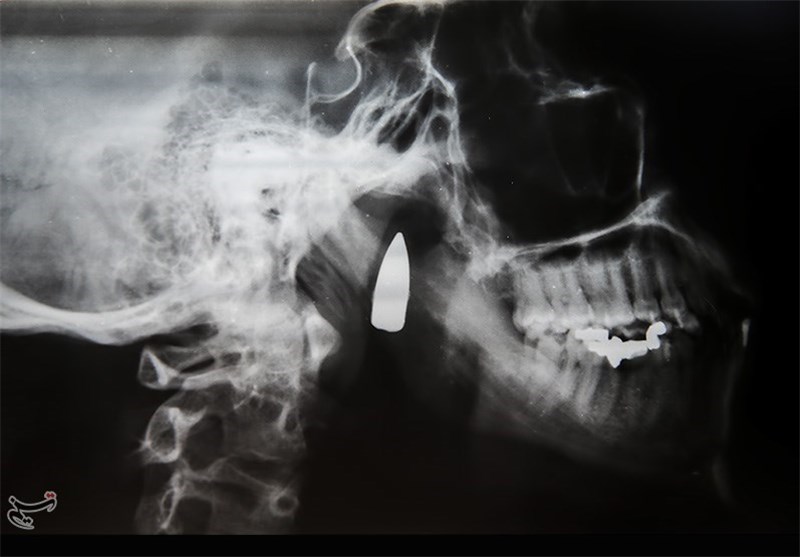

گردان امام سجاد(ع)، گردان محکم و جنگ دیدهای بود به راحتی عقب نشینی نمی کرد. معولا یک گردان 300 نفره که عملیات انجام می دهند هر 300 نفر ورزیده نیست. اما گردان امام سجاد(ع) از آن گردانهای پای کار بود. مرحله عملیات به جایی رسیده بود که باید تکلیف روشن شود. در میدان مین گیر کرده بودیم که عراقی ها آمدند. ما خط پدافند را جلوتر رفته بودیم 10 یا 15 نفر باقی مانده بودیم. عراقیها به همه تیر خلاصی میزدند. هوا داشت روشن می شد که یک تیر خلاص هم با کلاشینکف به من زدند. تیر به فکم اصابت کرد. من دیگر چیزی نفهمیدم. تا روز آزادی خرمشهر که در بیمارستان طالقانی اهواز بودم. به هوش آمدم دیدم زندهام و شهید نشدهام. از آنجا مرا به تبریز اعزام کردند دهانم را با سیم بسته بودند و نمیتوانستم حرفی بزنم. جای بدی تیر خورده بود. این تیر هنوز هم در فکم به جا مانده است. و به خاطر حساسیت عصبی که نزدیک آن قرار گرفته نتوانستهاند آن را جراحی کرده و بیرون بیاورند. امکان ام آر آی هم وجود ندارد چون باعث تکان خوردن جسم خارجی و صدمه به اعصاب میشود. فقط عکس رادیولوژی از آن دارم که نشان میدهد این گلوله هنوز در فکم وجود دارد.